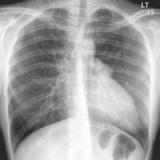

Case 1 PA

Peric calcification